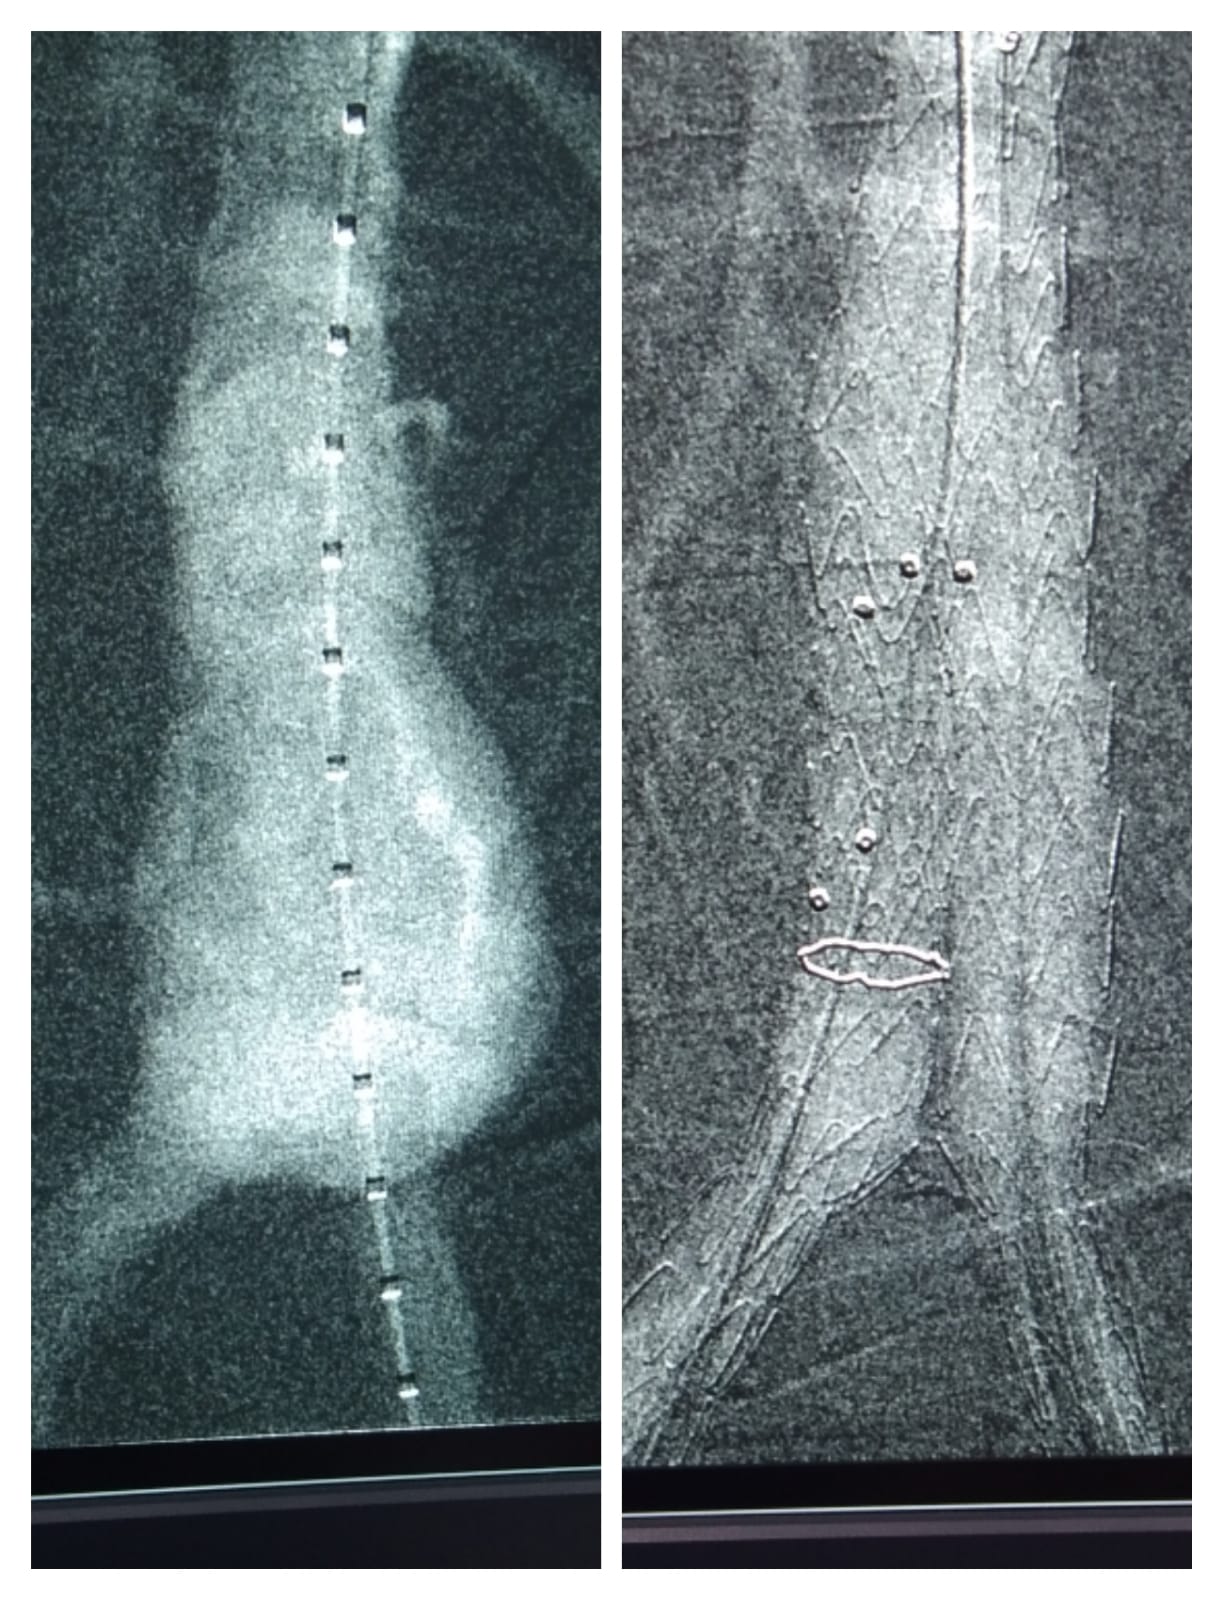

Deep Vein Thrombosis (DVT) in left leg. Pre Procedure - No Flow & Post Procedure- Complete flow restoration post thrombolysis & Thrombectomy.